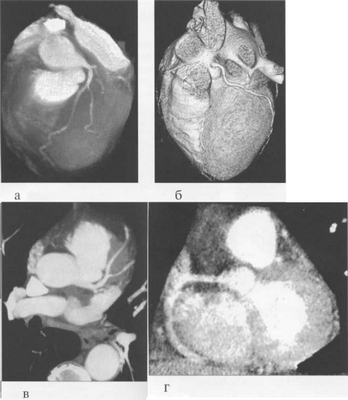

Рис. 9.36. МСКТ-коронарограммы.

а, б — VRT-реконструкции; в — проекция максимальной интенсивности; г — многоплоскостная реформация.